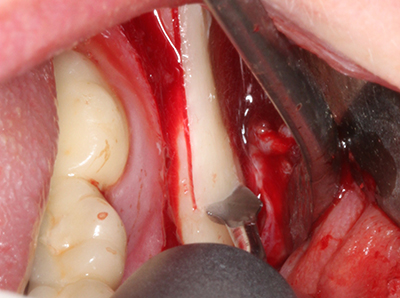

Fig. 18: Preparación de una tapa cortical con la sierra ósea piezoeléctrica (Piezomed, W&H).

Fig. 19: Zona operada después de neurolisis y eliminación del osteomo.

Fig. 20: La tapa ósea extraída se readapta y se fija mediante un tornillo para osteosíntesis (KLS Martin, Tuttlingen).

Si es preciso realizar intervenciones quirúrgicas en las que el hueso está en contacto directo con estructuras sensibles, como son los vasos sanguíneos o los nervios, los instrumentos rotativos presentan un enorme potencial de provocar lesiones iatrogénicas. Así, precisamente en la representación de nervios después de una lesión iatrogénica, o en el transcurso de la lateralización de un nervio para resecciones, reconstrucciones o incorporación de implantes, los equipos piezoeléctricos pueden resultar muy útiles para preparar la tapa ósea y retirar las partes de tejido duro cercanas al nervio (fig. 17-20). Por lo general, un ligero contacto del cordón nervioso con el inserto piezoeléctrico no tiene consecuencia alguna; ahora bien, un procedimiento poco cuidadoso con movimientos tipo sierra o piezas de trabajo sobre la base ósea aún existente puede provocar lesiones nerviosas temporales o incluso permanentes. Con todo, el riesgo de sufrir una lesión de este tipo se considera significativamente inferior que en los casos en los que se utilizan sierras y fresas (Pereira, Gealh et al. 2014).